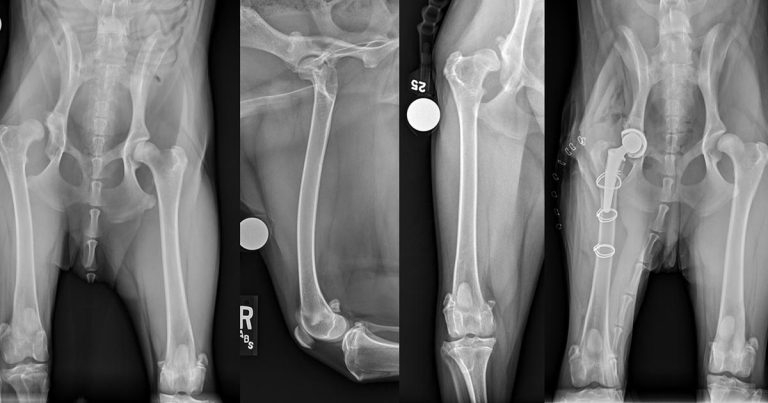

Figure 1. Pre and postoperative ventrodorsal view of the pelvis and orthogonal views of the right femur after total hip replacement for treatment of chronic luxation of the right hip. The pain associated with the osteoarthritis in this 12-month-old labradoodle did not respond satisfactorily to non-surgical management.

Joint replacement is the gold standard in human medicine, but has only been available for small animals for approximately the past 40 years. Since that time, vets have continued to perfect the most common joint replacement (total hip replacement; THR; Figure 1), even creating innovative solutions for dogs with challenging anatomy that precludes placement of the standard femoral stem. To date, published results appear to be positive (Liska et al, 2009), but joint replacement is still in its early stages for joints such as the knee and elbow. Additionally, replacement of other joints, such as the shoulder (Sparrow and Fitzpatrick, 2013; Fitzpatrick et al, 2013) and ankle, remains experimental at this time.